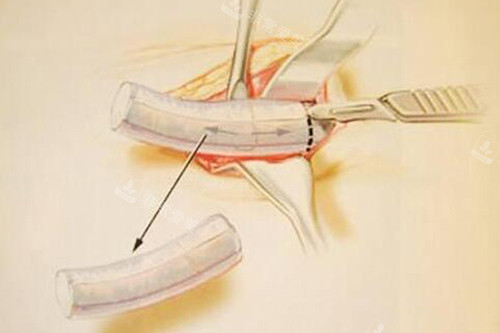

第三点是“筋膜包裹技术”。

这是对抗肋骨软骨吸收的一大利器。

朴院长在取肋软骨时,会创新性地保留一部分肋骨表面的筋膜。

然后在雕刻好软骨支架后,用这层自体筋膜把它包裹起来。

这样做能显著降低软骨移植后被身体吸收的比率。

确保术后鼻子的形态和高度能够长期维持,不会因为吸收而慢慢变矮。